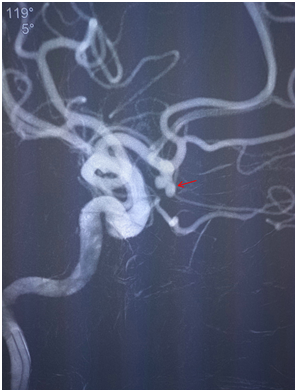

医生首先给李先生做了脑血管造影检查,如前所料,发现左侧前交通动脉瘤。神经内科张斌主任主持全科及神经外科张显强医师进行跨科室讨论,经积极的术前准备,决定急诊行颅内动脉瘤微弹簧圈介入栓塞术。介入手术在我院新引进的大型C臂飞利浦DSA机下完成。在张斌主任指导下,由张显强副主任医师主刀完成,术中发现动脉瘤约5mm大小,远端已形成破裂小泡,如不及时治疗,一旦再次破裂,后果不堪设想。经过1小时紧张的手术,在动脉瘤内填塞入4枚微弹簧圈,顺利结束手术。目前患者已康复出院,患者家属对治疗结果非常满意。

箭头所指为前交通动脉瘤